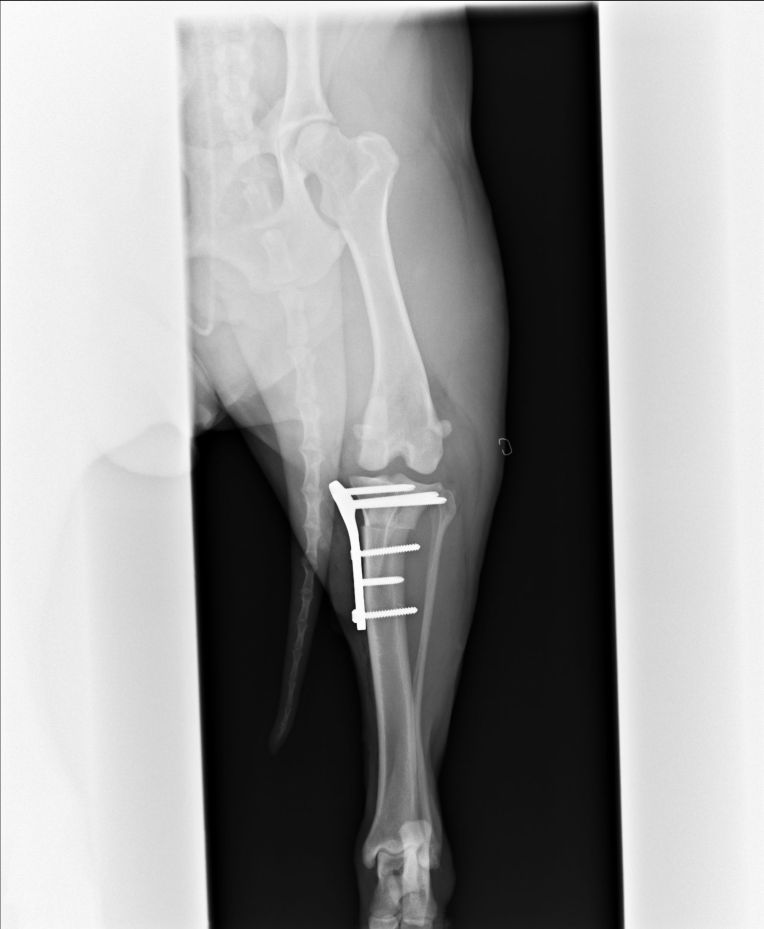

脛骨の先端を、専用のノコギリで切断しようとしてるとこですかね・・・。

多分こちらは切断した部分に角度をつけて、プレートで固定してるとこ。

手術後のレントゲンで、きちんとプレートが付いている事も確認。